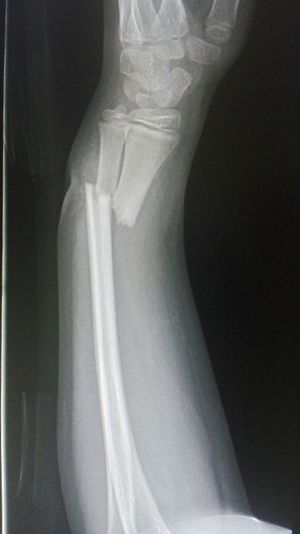

Xray

Fracture